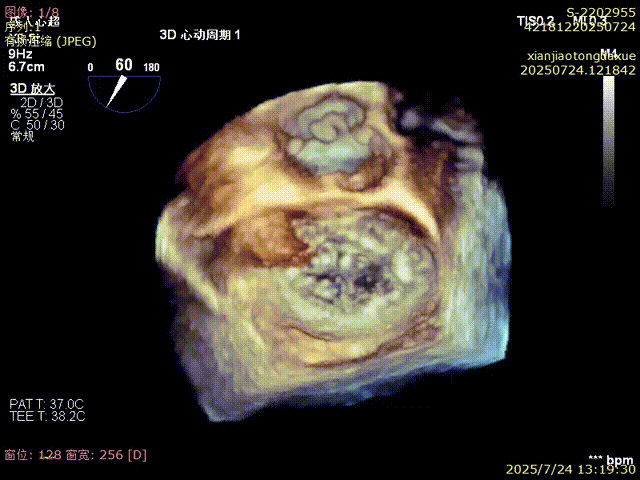

3D确认夹合位置

3D视角下反流情况